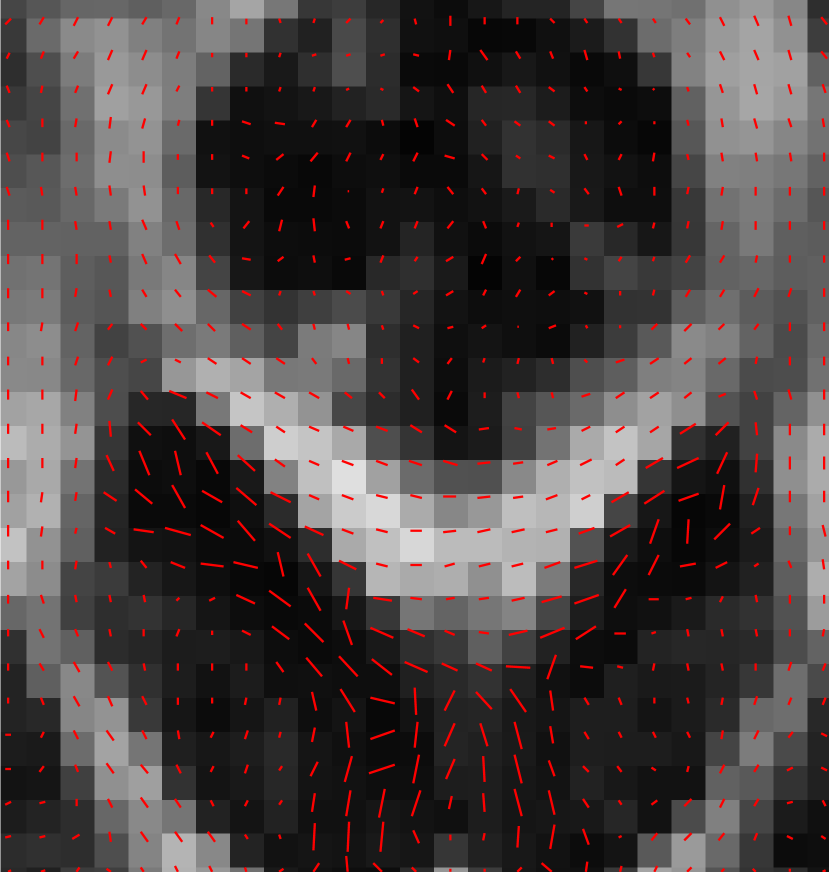

The numerical results are in Table 1 and Figures 3–5, with the first of the figures showing the colour-coded principal eigenvector of the reconstruction, the second showing the fractional anisotropy and principal eigenvectors, and the last one the errors in the latter two, in a colour-coded manner. All plots are masked to represent only the non-zero region. The field of fractional anisotropy is defined for a field of 2-tensors on as

with denoting the eigenvalues of . It measures how far the ellipsoid prescribed by the eigenvalues and eigenvectors is from a sphere, with corresponding a full sphere, and corresponding to a degenerate object not having full dimension.

As we can see, the non-linear approach (3.2) performs overall the best by a wide margin, in terms of the pointwise Frobenius error, i.e., error in . This is expressed as a PSNR in Table 1. What is, however, interesting, is that the constraint-based approach (3.5) has a much better reconstruction of the principal eigenvector angle, and a comparable reconstruction of its magnitude. Indeed, the 95% confidence interval in Figure 3(g) and Figure 4(g) suggests a nearly perfect reconstruction in terms of smoothness. But, the Frobenius PSNR in Table 1 for this approach is worse than the simple unregularised inversion by regression. The problem is revealed by Figure 5(f): the large white cloudy areas indicate huge fractional anisotropy errors, while at the same time, the principal eigenvector angle errors expressed in colour are much lower than for other approaches. Good reconstruction of the principal eigenvector is important for the process of tractography, i.e., the reconstruction of neural pathways in a brain. One explanation for our good results is that the regulariser completely governs the solution in areas where the error bounds are inactive due to generally low errors. This results in very smooth reconstructions, which is in the present case desirable as our synthetic tensor field is also smooth within the helix.

The results are in Table 2 and Figures 6–8, again with the first of the figures showing the colour-coded principal eigenvector of the reconstruction, the second showing the fractional anisotropy and principal eigenvectors, and the last one the errors in the latter two, in a colour-coded manner. Again, all plots are masked to represent only the non-zero region. In the figures, we concentrate on error bounds based on 95% confidence intervals, as the results for the 90% and 99% cases do not differ significantly according to Table 2.